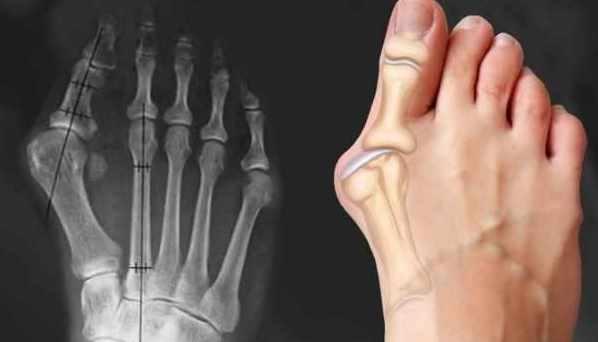

Суставы (остеоартрит). Что такое артроз, как он развивается, тесты на артроз, принципы и схемы лечение суставов. Синий